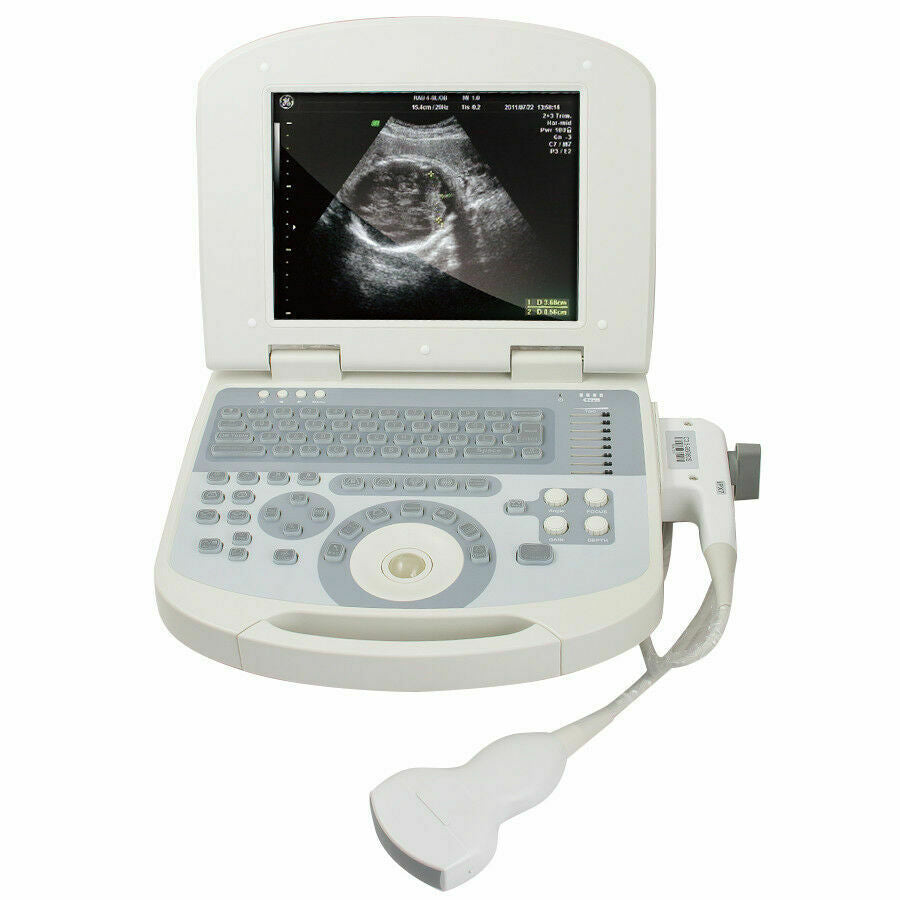

The New Portable Notebook Digital Laptop Machine Ultrasound Scanner is a groundbreaking device that has revolutionized the field of portable diagnostic imaging. With its advanced features and lightweight design, it is an ideal tool for medical professionals who need to perform ultrasound scans in various settings. This remarkable machine combines cutting-edge technology with convenience, making it an essential addition to any healthcare provider's toolkit.

Designed with portability and functionality in mind, the New Portable Notebook Digital Laptop Machine offers superior performance without compromising on ease of use. Its compact size allows for easy transport and setup, while the digital laptop interface ensures that users can quickly access and utilize the scanner's capabilities. The inclusion of a convex probe and 3D imaging further enhances the diagnostic accuracy, providing clearer and more detailed images than ever before.

One of the key advantages of this ultrasound scanner is its versatility. It can be used in a wide range of medical scenarios, including emergency rooms, ambulances, and remote clinics. The New Portable Notebook Digital Laptop Machine is particularly valuable in situations where traditional, bulky ultrasound machines would be impractical. Because of its battery-operated design and robust construction, it can withstand the demands of frequent use in diverse environments.

Moreover, the New Portable Notebook Digital Laptop Machine Ultrasound Scanner features an intuitive user interface that simplifies the ultrasound process. Medical professionals can easily navigate through the software, customize settings according to their needs, and save images for later review. This level of user-friendliness ensures that both experienced practitioners and those new to ultrasound technology can effectively operate the device, improving patient care outcomes.

In addition to its user-friendly design, the New Portable Notebook Digital Laptop Machine provides high-resolution imaging that is crucial for accurate diagnostics. The 3D imaging capability allows for more comprehensive assessments of anatomical structures, leading to better treatment planning and patient management. Whether used for routine check-ups or complex medical evaluations, this ultrasound scanner delivers reliable and precise results.

The durable design of the New Portable Notebook Digital Laptop Machine Ultrasound Scanner makes it a long-lasting investment for any medical practice. It is built to withstand the rigors of daily use and is backed by extensive support and maintenance options. This ensures that healthcare providers can continually rely on the machine to deliver exceptional performance.

Overall, the New Portable Notebook Digital Laptop Machine with Ultrasound Scanner and Convex Probe+3D is a state-of-the-art tool that embodies innovation, portability, and efficiency. It empowers medical professionals to provide high-quality care in various scenarios and enhances the overall diagnostic process. Investing in this advanced ultrasound machine is a step towards improving patient outcomes and expanding the capabilities of ultrasound imaging in modern medicine.